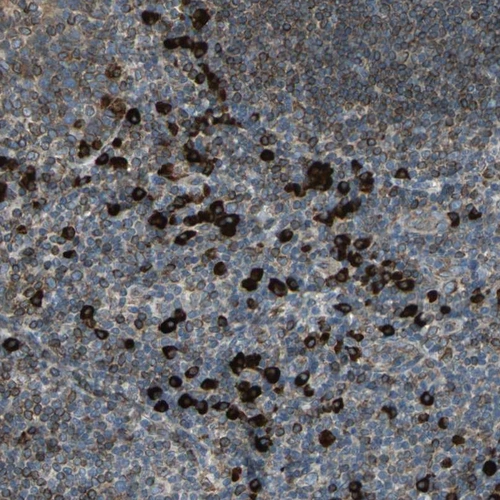

Immunohistochemical staining of human cerebral cortex, lymphoid tissues, pancreas and skeletal muscle using Anti-SYVN1 antibody HPA005480 (A) shows similar protein distribution across tissues to independent antibody HPA024300 (B).